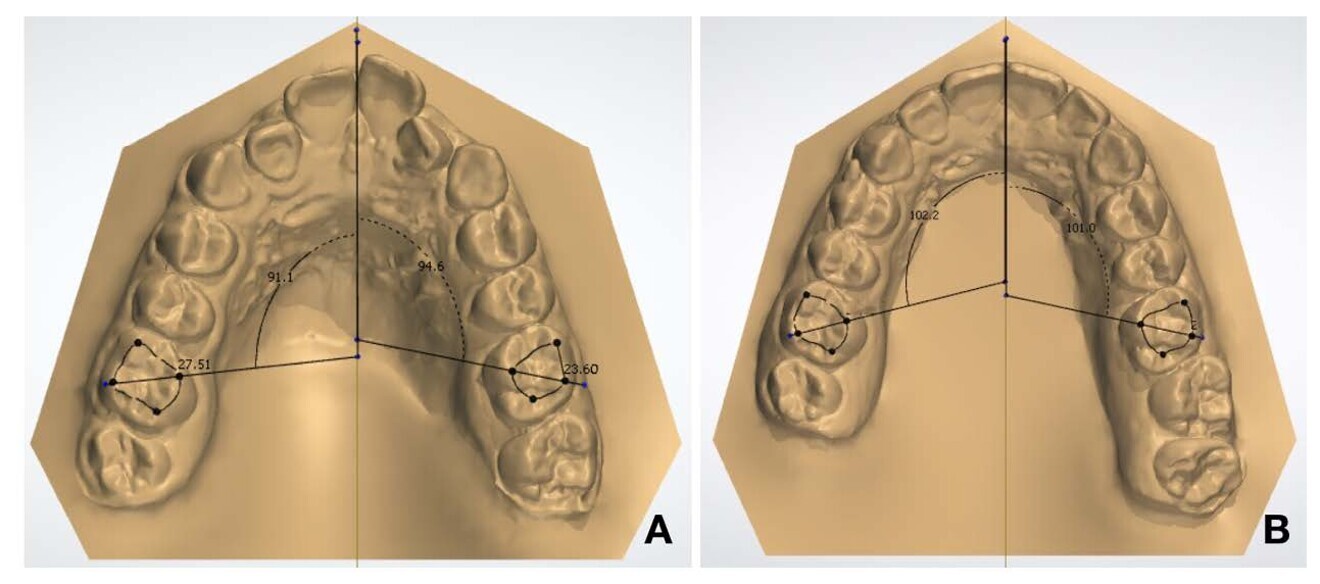

To assess the changes more graphically, we scanned the pre- and post-treatment models to compare the changes that had taken place from when we started the treatment until we had finished the treatment using 3Shape Dental System. For the first comparison, the sagittal plane was taken as a reference, drawing two lines from the cusp of the canine and the mesial-vestibular cusp of the first molar to the sagittal plane. This comparison was repeated in both arches and in both models. The models were then superimposed to measure the movement that had taken place during the treatment. The distance between the canine cusp in the pretreatment model and the canine cusp in the post-treatment model was measured, from which it was determined that the canine in the maxillary right quadrant had moved by 2.57 mm in the distal direction. In the maxillary left quadrant, the canine had moved by 2.06 mm. The distalisation of the first maxillary molar was 1.48 mm for the right quadrant and 1.86 mm for the left quadrant (Fig. 22).

The extent of molar de-rotation was quantified by drawing a line that crossed the distobuccal cusp and mesiopalatal cusp to the sagittal plane and measuring the angles formed between that line and the sagittal plane of both models (Fig. 23). The post-treatment model showed an increase in the rotation angle of 11.1° for tooth #16 and of 6.4° for tooth #26. This was a significant de-rotation of the first molars.

Figs. 22a–c: (a) Pretreatment model. (b) Post-treatment model. (c) Overlap of the two models, orange corresponding to the pretreatment model and green to the post-treatment model (images generated using 3Shape Dental System).

Figs. 23a & b: (a) Pretreatment first molar angulation. (b) Post-treatment first molar angulation (images generated using 3Shape Dental System).